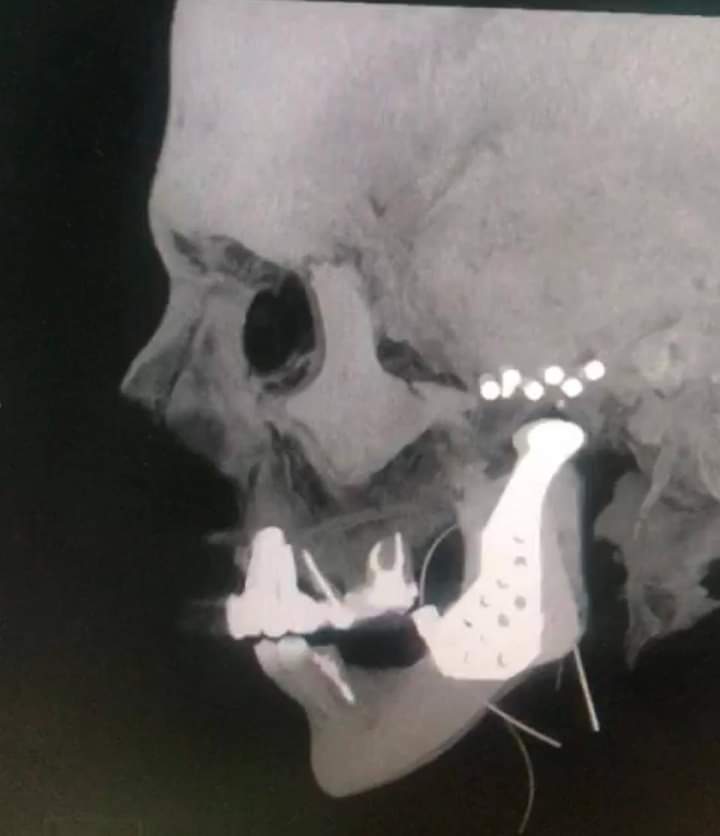

تمكن قسم الجراحة الخاصة / شعبة جراحة الوجه والفكين في مستشفى الملك المؤسس عبدالله الجامعي من إجراء عملية نوعية لمريضة في الأربعين من العمر كانت تعاني من خلع متكرر في المفصل الصدغي وتكلسات شديدة من الجهتين وخلع متكرر في المفصل أثناء الحركة.

وأجرى العملية فريق طبي بإشراف إستشاري جراحة الوجه والفكين الدكتور تيسير الخطيب حيث استغرقت العملية (4) ساعات تمكن الفريق من زراعة مفصل صدغي صناعي في الجهتين بعد كسر وازالة المفصل الصدغي المتكلس والمتأكل وتعتبر هذه العملية من العمليات المعقدة والصعبة حيث أظهر الفحص السريري وصور الاشعة الطبقية وجود تآكل في المفصل الصدغي وتكلسات شديدة محيطة برأس المفصل مما يودي الى حدوث خلع متكرر والالام في منطقة المفصل والأذن والرقبة .

وأشار الدكتور الخطيب إلى أن معاناة المريضة تمثلت في عدم القدرة على فتح الفم نهائيا وصعوبة بالغة في المضغ وأضرابات في النوم بسبب الآلام في المفصل الصدغي من الجهتين مبيناً إن هذه العمليات يجريها بالعادة فريق جراحين متخصصين في مراكز متخصصة مثل هذا المركز الجامعي المميز والمجهز بأحدث الأجهزة والذي يشهد تقدماً كبيراً.